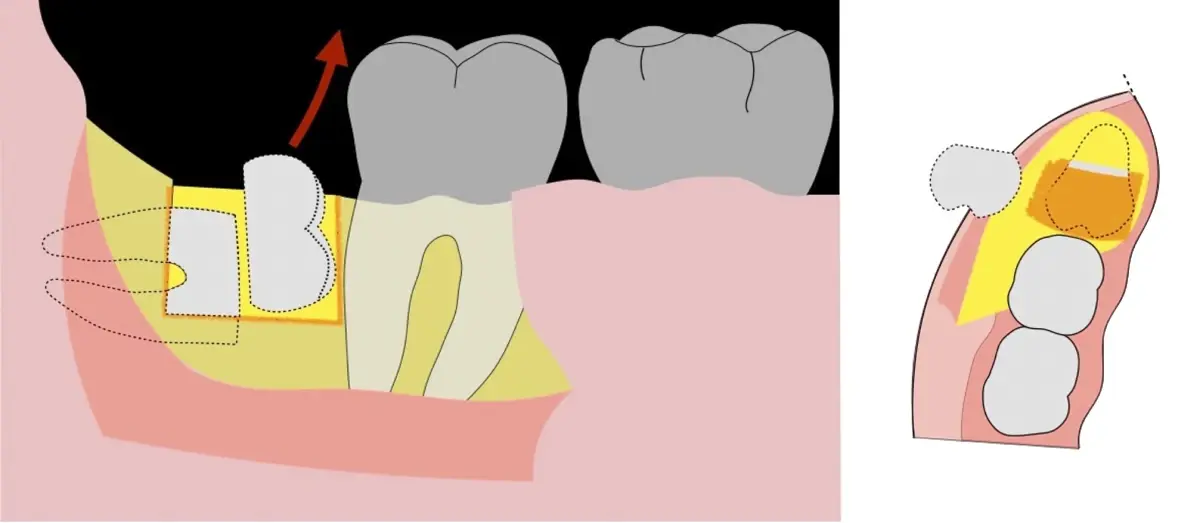

Figura 8. Odontosección mediante fresa de alta rotación y/o inserto de corte de piezoeléctrico. Posteriormente se procede al ensanchamiento del espacio pericoronario con el periótomo de piezoeléctrico para facilitar la avulsión de la pieza dentaria.

Figura 9. Avulsión de la parte coronaria de la tercera molar.

Figura 10. Tracción mesial del remanente dentario utilizando botadores en bandera.

Figura 11. Avulsión del remanente radicular de la tercera molar.